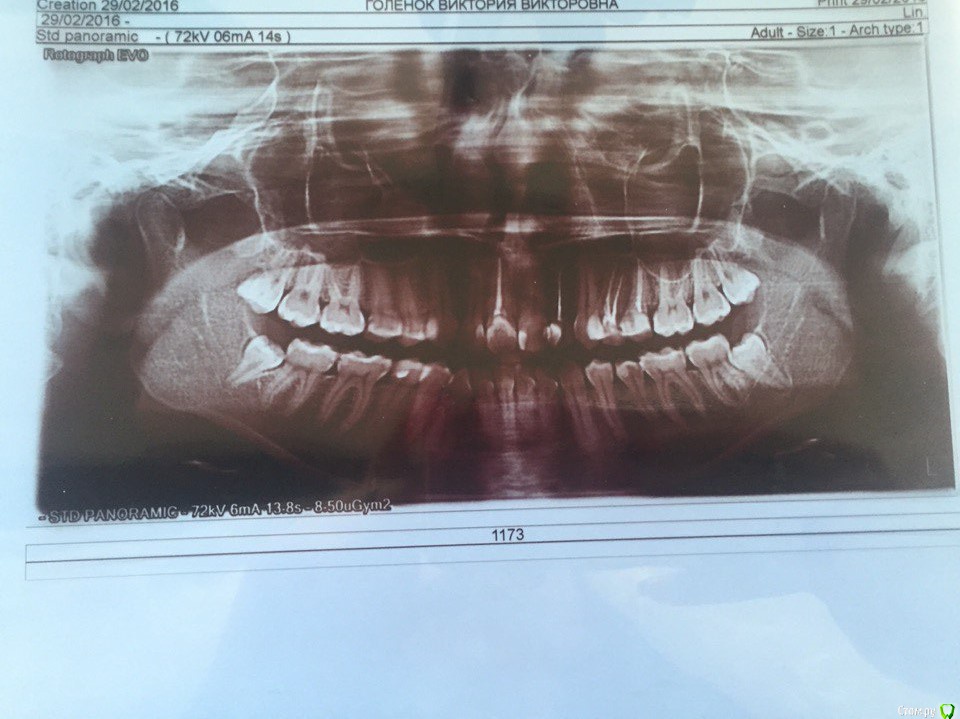

установка брекетов, удаление четырех четверок, требуется консультация

Здравствуйте! Мне 23 года, хотела бы получить консультацию. Одним ортодонтом мне было предложено удалить четыре четверки с последующем ношением брекетов в течение 1,5 лет. Другой доктор сказал, что можно удалить только по одной четверке слева вверху и внизу. В связи с этим подскажите, пожалуйста, какие зубы мне действительно стоит удалять и какова вероятность получения хорошего результата? и обязательно ли исправлять оба зубных ряда, так как дискомфорт мне доставляет по большей части только верхний ряд. в верхнем ряду у меня 4 мертвых зуба, в том числе одна четверка.

информация не вся (многое в клинике в кресле смотрится )

но  по этим данным я бы ничего (кроме восьмерок) не удаляла.